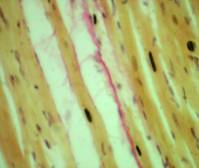

При микроскопическом исследовании миокарда у

умерших наркоманов, где стаж употребления марихуаны более 5 лет, обнаружены

следующие морфологические особенности: сетчатый

фиброз миокарда (Рис.1) и «веерообразные» гипертрофированные миокардиоциты с отеком сарколеммы, фиброз,

липоматоз стромы миокарда (Рис.2).

Рис.1.

Б-ной Г., 28л. Стаж каннабисной наркомании 5л. Сетчатый фиброз

миокарда.

Окраска

пикрофуксин по ван-Гизон; х 200